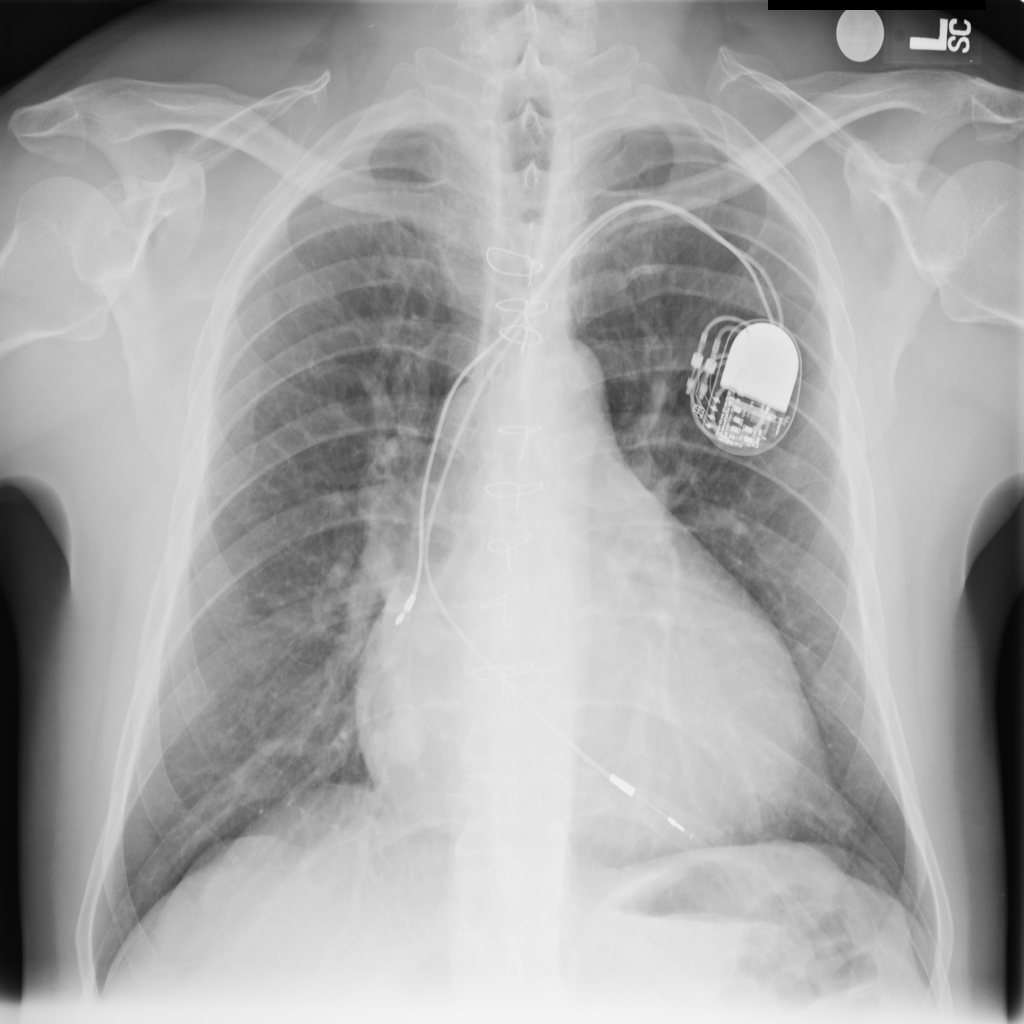

PAT-AE5C · IMG-000Cardiomegaly

PAT-AE5C · IMG-000

PA